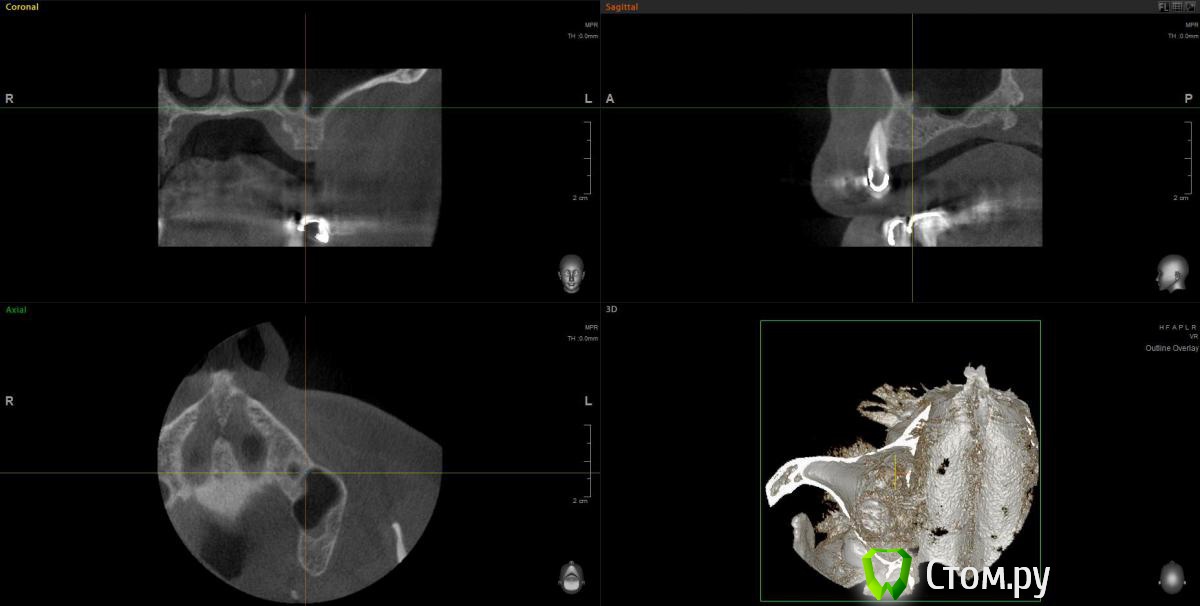

wladdX Опубликовано 11 февраля, 2014 Поделиться Опубликовано 11 февраля, 2014 (изменено) Прошу прощения за вторжение в чужую тему (администратор, поправьте), но ситуация похожа. Т.е. помимо синус-лифтинга надо увеличить ширину альвеолярного отростка. Предполагаю поступить примерно, как продемонстрировал Mane выше. Но может подойдёт "метод полужёстких каркасов? Кстати септа в пазухе замысловатая. По поводу остальных сегментов и прочих проблем - пациент на них не настроен, интересует его только зона 25,26,27 Изменено 11 февраля, 2014 пользователем wladdX Ссылка на комментарий

Sahan Опубликовано 11 февраля, 2014 Поделиться Опубликовано 11 февраля, 2014 Ну для планирования такой работы при КТ во рту должен был быть хирургический шаблон. А так никаких проблем. Открытый синус , плюс имплантаты , плюс сетка. Ссылка на комментарий

wladdX Опубликовано 12 февраля, 2014 Поделиться Опубликовано 12 февраля, 2014 Да, отсутствие шаблона при КТ, недочёт Хотя wax-up то сделан, недоработка, будем исправляться.По поводу сетки как-то не подумал даже, вероятно, потому что пока не пользовался. Возникает вопрос - для НКР под сеткой не слишком протяжённый дефект? Опасаюсь как-то в данной ситуации сразу имплантировать, первичной стабильности, скорее всего, не получить. Хотя сама по себе идея мне очень нравится: менее травматично и технически проще. Вот и чешу репу Ссылка на комментарий